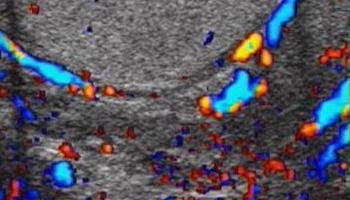

- Naczyń powrózka nasiennego (ocena ewentualnych żylaków).

- Żylaki powrózka nasiennego.